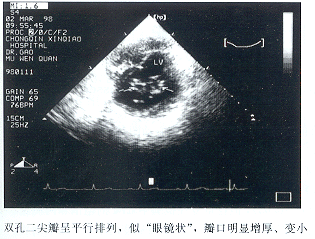

6例中手术前超声提示有DOMV 4例,此4例在2DE左室长轴或心尖二腔观调整声束方向,均可获得二尖瓣呈“V”型双开口征象(图1)。二尖瓣口短轴观察到两个分离的孔口,呈左右并列位或不在同一平面的左前右后位,瓣口大小接近或不等(图2)。有3例在心尖二腔或四腔观二尖瓣口处分别观察到2股舒张期血流柱进入左室。2例DOMV漏诊。伴有的其它畸形及异常均有相应的超声征象,术前超声均诊断正确,详细结果见表1。

过去认为DOMV极罕见,随着超声诊断技术的发展,其在先心病中的发病率有待人们重新评价。国内很少有人报告DOMV,掌握DOMV的超声特征将有助于人们对DOMV的检出,国外文献报告DOMV的超声特征如下:心尖二腔观二尖瓣呈“V”型,“海欧征”(Seagullsign)〔1〕 ,二尖瓣口短轴观呈“眼镜状”〔2〕 ,每个瓣孔分别获得相应的舒张期血流。本组病例观察到的DOMV超声表现同上,即长轴观二尖瓣双开口呈“V”型,短轴观呈两个分离的孔口,我们体会最容易诊断DOMV的超声征象是二尖瓣口短轴观两个平行排列的分离孔口,当两个孔口不在同一平面,呈交错排列时,需调整声束才能观察到双孔征象,若检查不仔细,可能会漏诊。本组术前漏诊2例,是其原因之一,其次与检查者对DOMV缺乏认识以及满足于心内其它畸形的诊断有关,该2例术后复查仍可观察到DOMV超声征象。

图2 二尖瓣口短轴观

图3 双孔二尖瓣并风湿性瓣膜狭窄,二尖瓣口短轴观